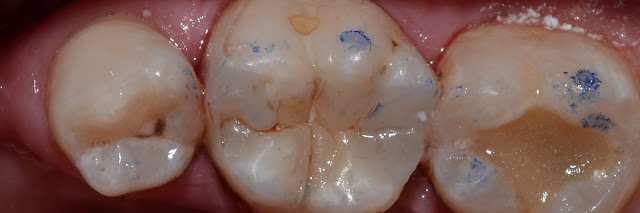

Каплан Опубликовано 26 марта, 2017 Автор Поделиться Опубликовано 26 марта, 2017 Скрытый 2 класс. Легче всего найти если подсветить контакт - как правило там есть трещинка. 4 Ссылка на комментарий

Каплан Опубликовано 26 марта, 2017 Автор Поделиться Опубликовано 26 марта, 2017 мезиально матрица мягко не айс....Не айс, там камень оставался. Я думал мягкий налет и слижется матрицей. Не слищало. Переставили конечно же. Фотку оставил, потому что просто показывает тем, кто без увеличения работает, на сколько оно важно. Хотя бы на фотках. Ссылка на комментарий